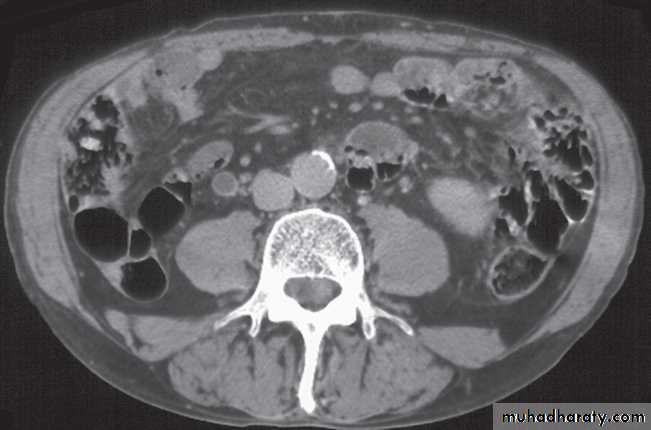

Computed tomography without intravenous contrast medium is exquisitely sensitive for the detection of calculi.

It is used in place of IVU for the detection and precise anatomical localization of stones prior to treatment in most centres

Computed tomography is now widely used to evaluate urinary tract obstruction .In acute obstruction, non-contrast enhanced CT sensitively demonstrates calculi and the unopacified, dilated collecting system can frequently be traced down to the point of obstruction .

Non-contrast CT is often used in acute ureteric colic, as an alternative to IVU, in patients with an allergy to intravenous contrast medium.